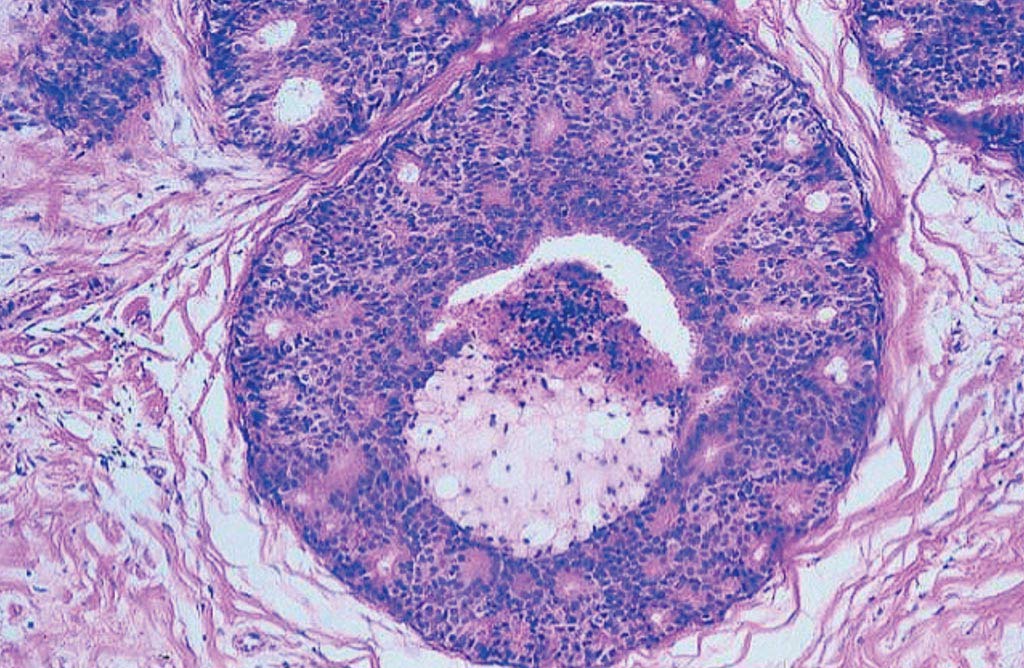

Исследование: микропрепарат молочной железы в медицине

Раздел: Снимки-откровения